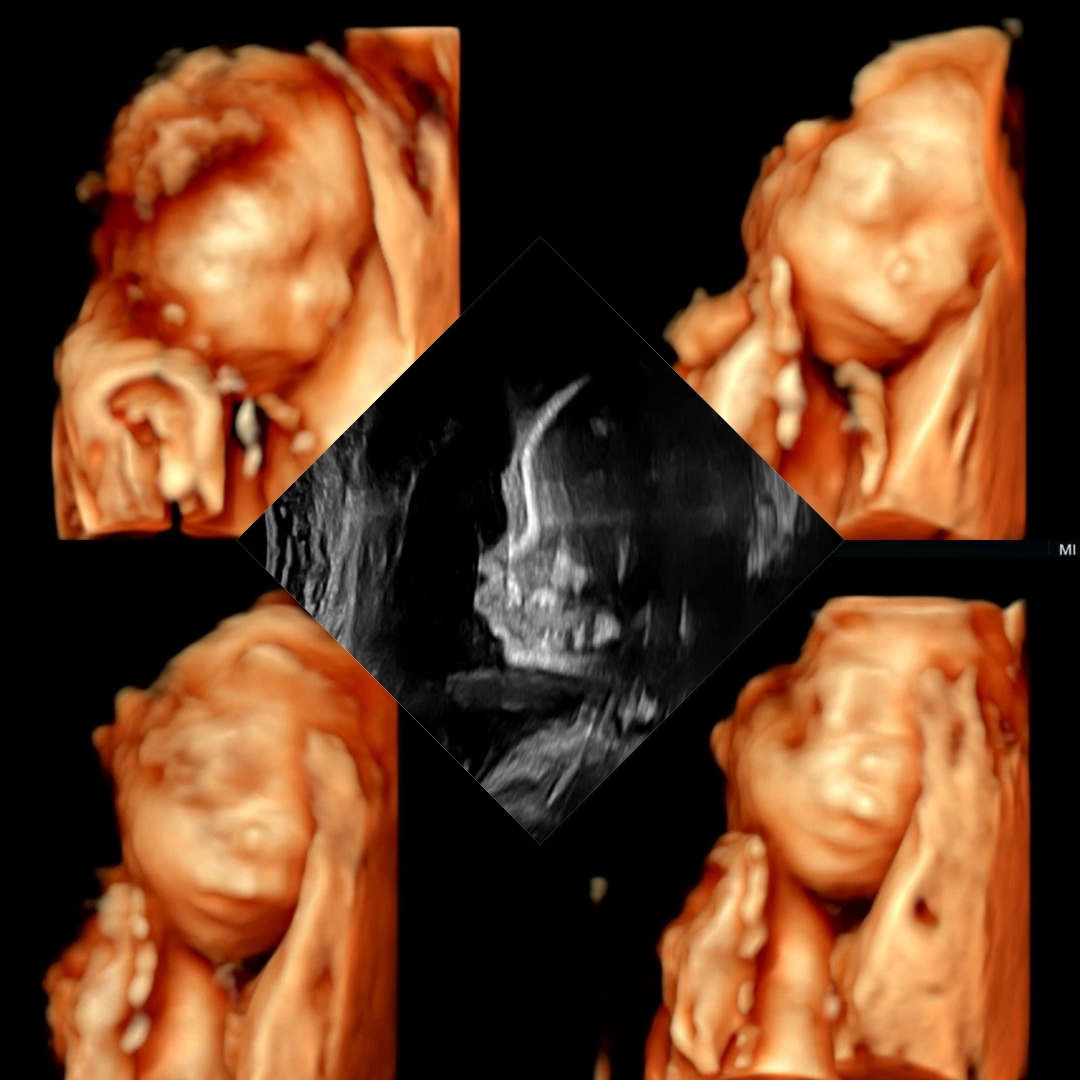

23주 3일 정밀초음파 보고 왔어용 아침 내내 활발하더니 정밀초음파 보기 시작하니 꼭 붙어 자버리네요 😂 얼굴 한 번 제대로 본 적 없는데 벌써 이렇게 말 안 들으면 어쩌자는겨 🤦♀️ 그와중에 엄마콩깍지인건지,, 콧대도 쫌 있는 것 같고,,, 입술은 쭉 내밀고 있는 것 같아서 귀엽긴 귀엽네요 😗 ㅋㅋㅋㅋ

이사진은 입체초음파인거죠~!?

네네~~ 저희 병원은 평소에도 그렇고 초음파 볼 때마다 입체초음파 간단하게 보여주시더라구요 ! 정밀초음파 보는 곳은 층도 다르고 원장님도 달라서 못볼줄알았는데 이거라도 건졌습니다 ㅎㅎㅎ